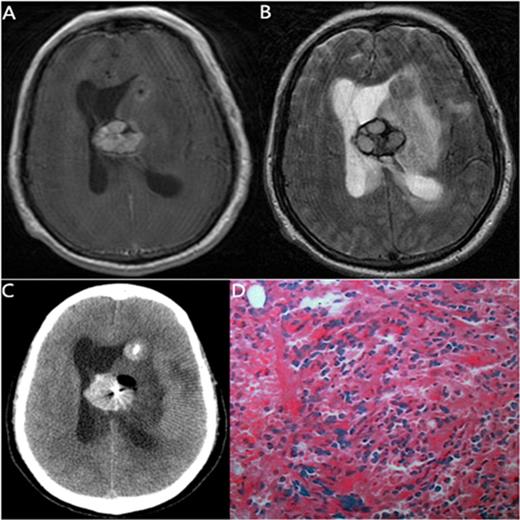

The MRI, biopsy site and pathology of a 60-year-old man with CMML